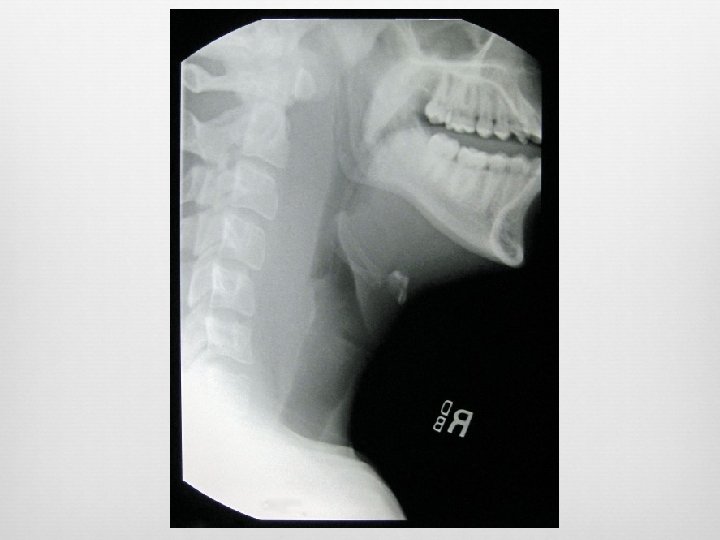

Foreign Body Visualization of radiopaque FB Widened pre-vertebral shadow Loss of lordosis Location Esophagus – coronal plane Trachea – sagittal plane (best seen on lateral)

Triple blinded prospective study 100 elective surgery patients Lateral neck x-ray compared with Mallampati Anesthesiologist gold standard (grade III or IV) Results Mallampati sens: 26% spec: 100% Lateral neck film: sens: 100% spec: 100%